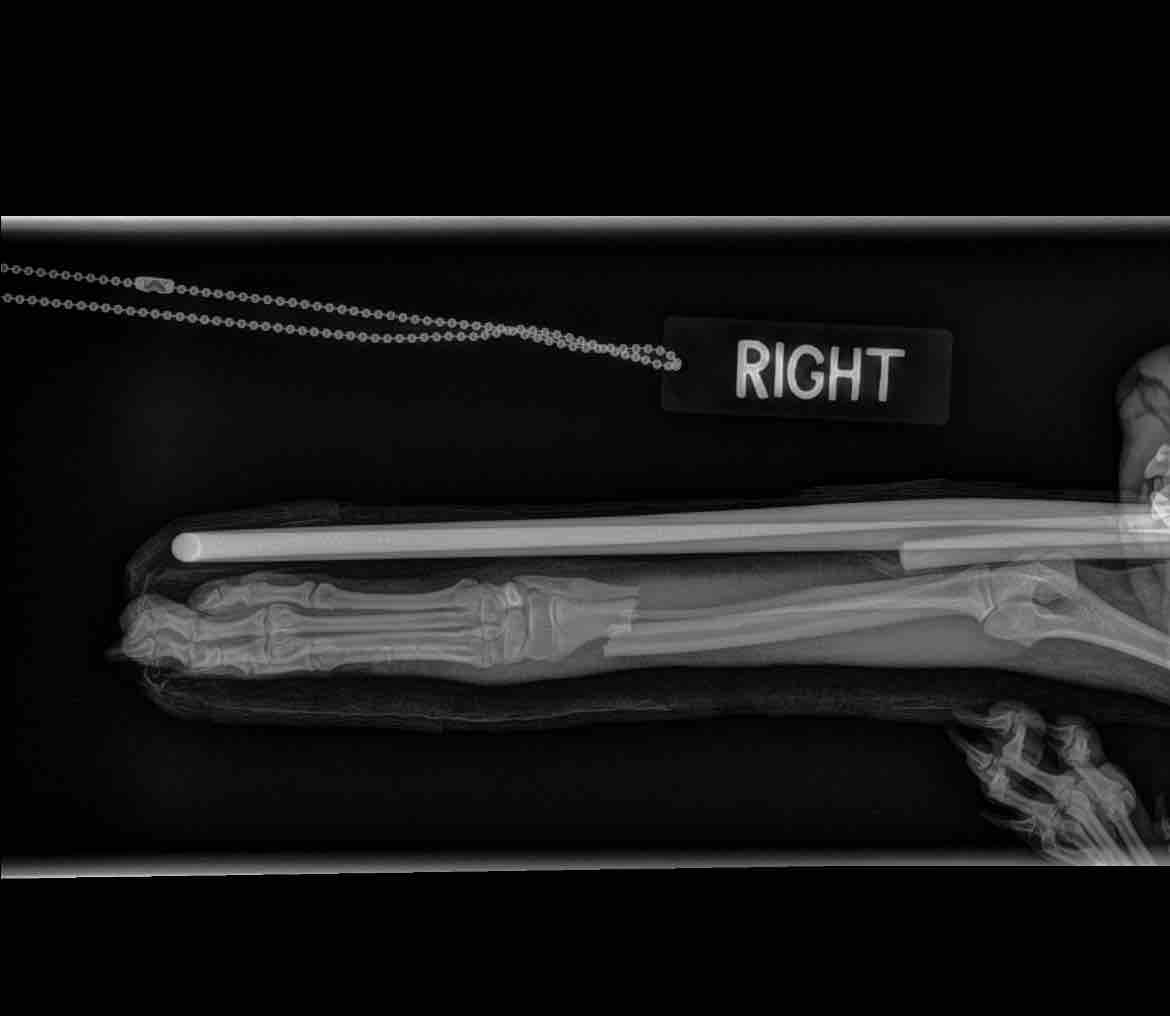

Poor little Butter is only 8 months old and he needs surgery to repair a broken radius and ulna on his front leg. He was playing with my niece, jumped up five feet in the air, fell and snapped his lower leg in half. His scream alone was heartbreaking.

I splinted his leg and he had a great morning except for when he forgot he’s hurt and stepped on his bad leg.

Exam, pain meds, x-ray, and splint were $1500.